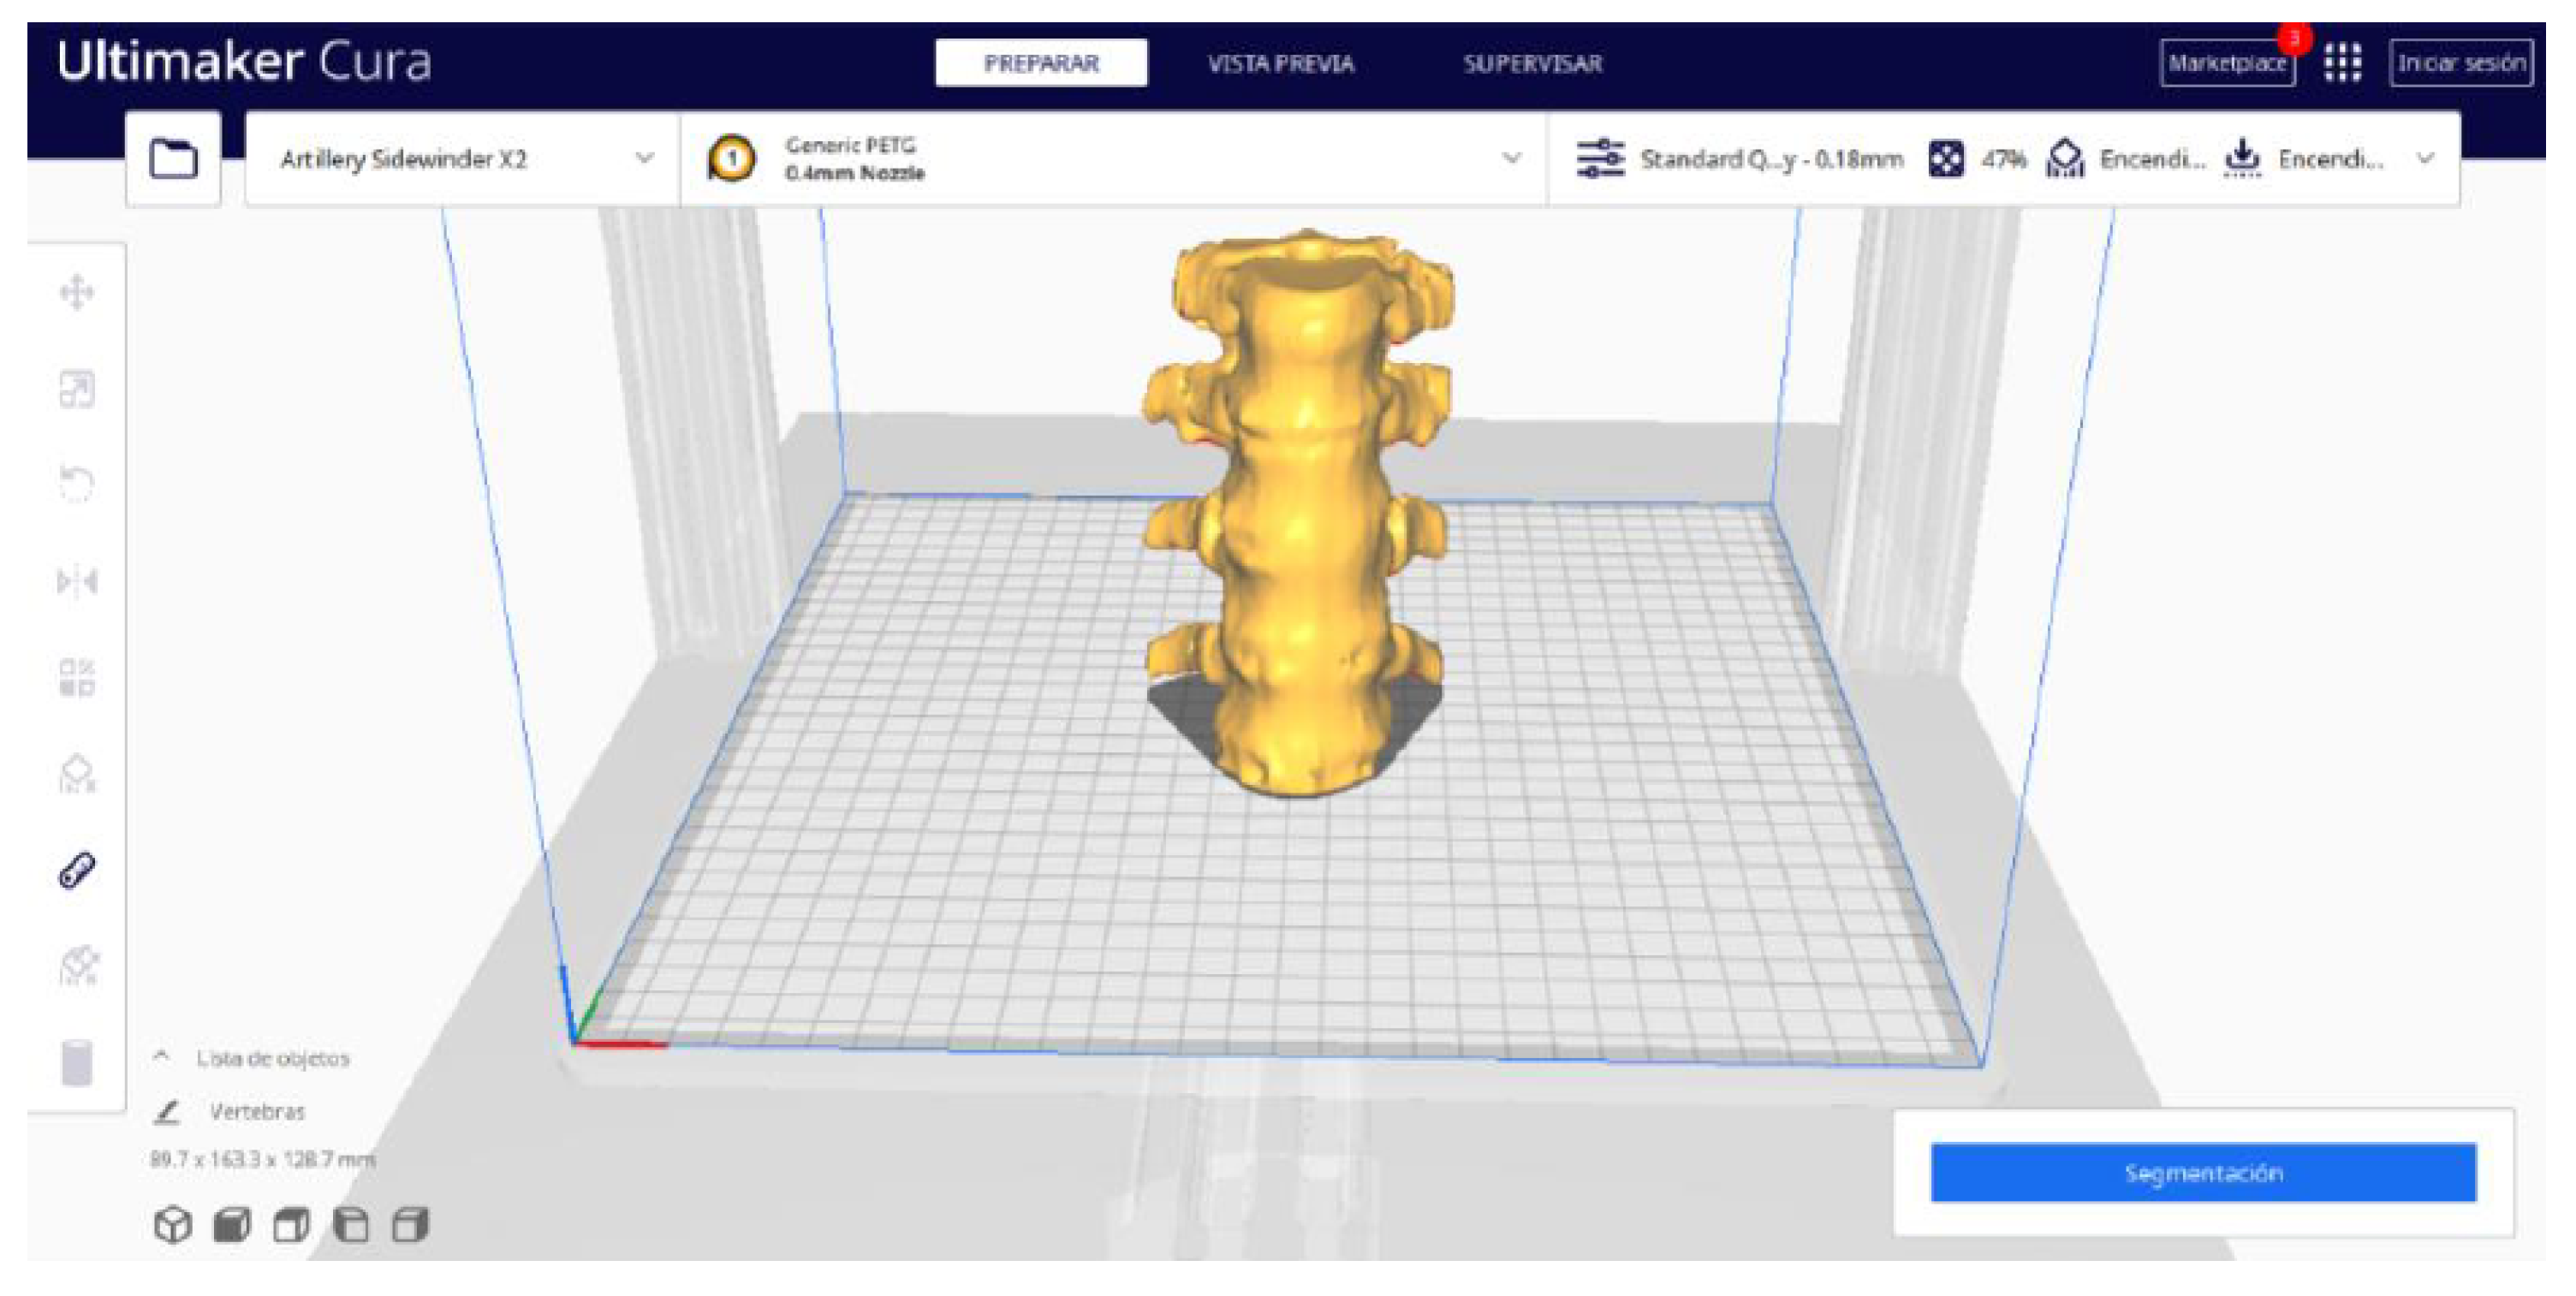

2.2. STL-to-GCODE File Conversion

- Launch the Ultimaker Cura program on your computer.

- Open the STL file you want to print from the “Open File” option in the menu.

- Access the printer settings within Ultimaker Cura.

- Be sure to select the appropriate printer model and material settings for your 3D printer.

- If necessary, make adjustments to the position, scale, or rotation of the model on the build platform within Ultimaker Cura. This allows you to optimise the layout of the model on the printing platform.

- In order to continue the STL file to GCODE conversion process, select the “Segmentation” option in Ultimaker Cura.

- The segmentation tool provides valuable information such as the estimated model weight and estimated printing time, among other crucial data.

3.1.2. STL-to-GCODE File

| Vertebrae | [150, 300] | Median | 0.8 | 0.18 | 25 |

| Vertebrae models | m; m | Artillery Sidewinder X2 |